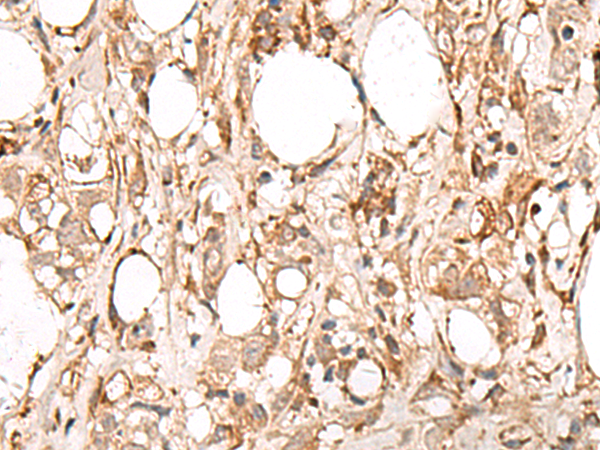

IHC positive control: |

Human esophagus cancer and Human breast cancer |

IHC Recommend dilution: |

50-300 |